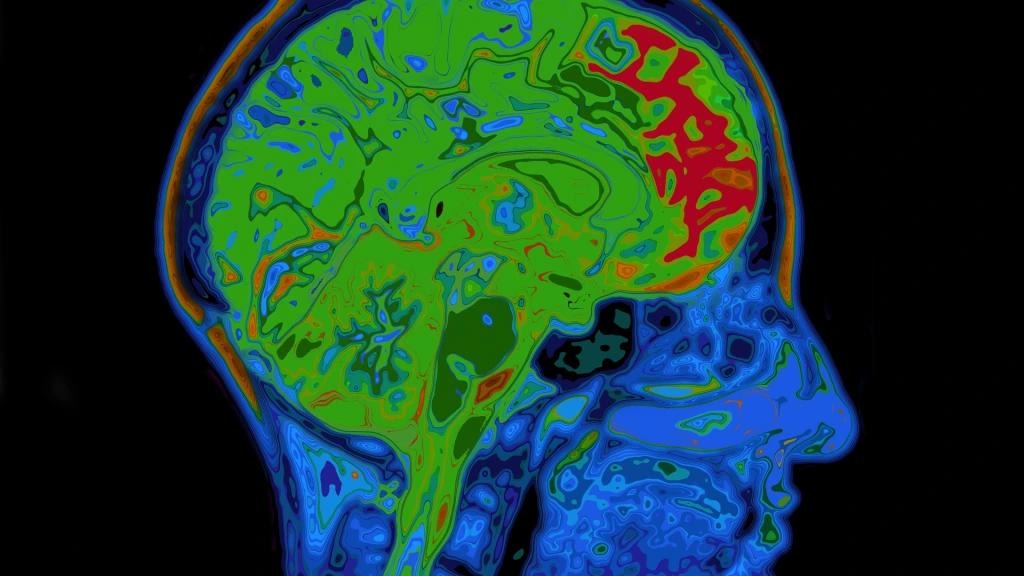

Image Credit: Frontiers